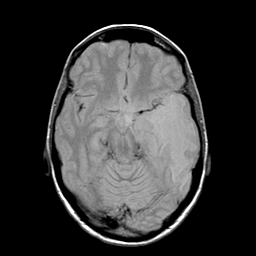

Metastatic bronchogenic carcinoma: proton density-weighted MR -- Slice #8

[Home][Help][Clinical] Slice 8